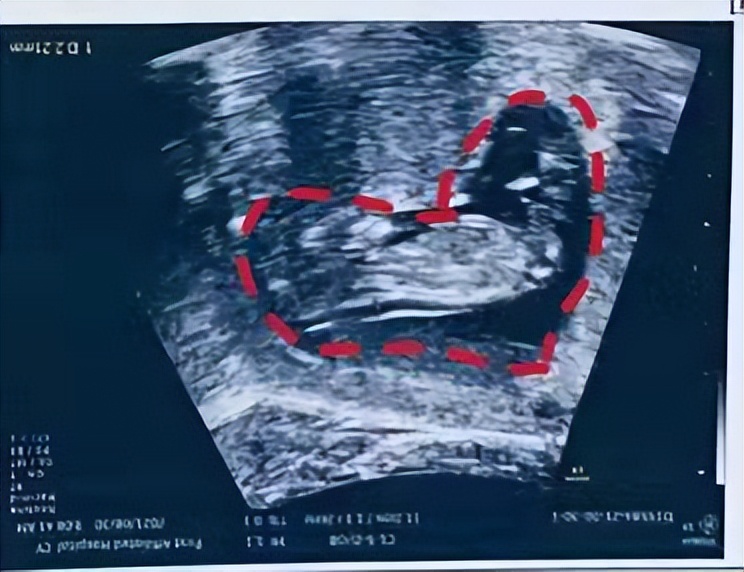

知道木木是在孕10周+的时候了,后悔没有早点知道木木,走了不少的弯路,跑了好多家医院,每天都在担心胚胎发育不好,犹记得第一次面诊木木的时候,他说我其他还好,就是血小板数值高,有高凝的风险,马上告诉我别太担心,遵医嘱用药,会没事的,给了我莫大的信心。让我把肝素每天一支,阿司匹林每天100mg用上,定期产检,按时复查就可以了,于是我就跟着木木的方案开始用药,知道肝素、阿司匹林是专门针对凝血方面疾病的,我安心了很多,超声NT宝宝都是爱你的形状。